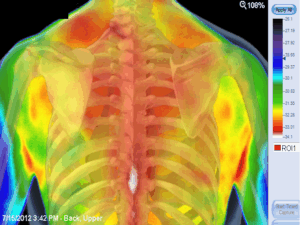

Borstweefseltherapie wordt regelmatig aangeraden door Medisch Thermografen in heel het land door de goede ervaringen in de ontwikkeling van de borstgezondheid, welke zij terug kunnen zien op de thermografische beelden.